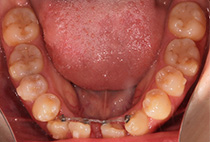

歯の大きさのバランスを整えるため、下は前歯を2本抜歯します。

しっかり噛めるようになりました。

かみ合わせが安定すると機能が改善、筋肉もバランスも整います。終了直後よりさらにきれいな唇になります。